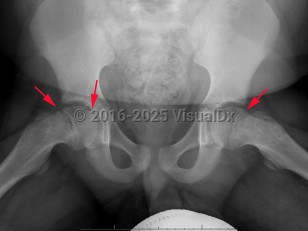

Another classification tool is the Southwick slip angle classification. This uses the epiphyseal-diaphyseal angle, which can be measured on both anteroposterior (AP) and frog-leg lateral pelvis imaging. SCFE can be classified as mild if the angle is less than 30 degrees, moderate if between 30 and 50 degrees, and severe if greater than 50 degrees.